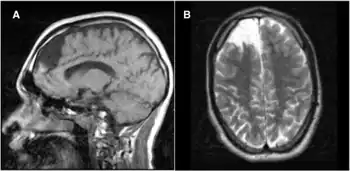

In many cases, propionic acidemia can damage the brain, heart, kidney, liver, cause seizures and delays to normal development such as walking or talking. The patient may need to be hospitalized to prevent breakdown of proteins within the body. Dietary needs must be closely managed.